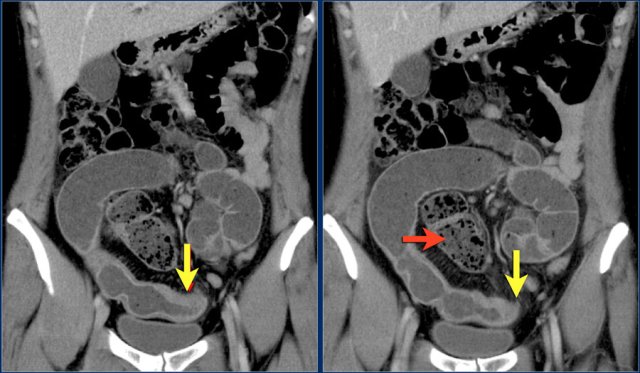

The red arrow indicates the sigmoid, which is filled with feces. So this is not a small bowel feces sign.

The findings are:

- Obstructing lesion in the ileum with shouldering leading to small bowel obstruction (yellow arrow).

One could consider the diagnosis of Crohn's disease.

However this patient was not known with Crohn's disease and the terminal ileum (not shown) was normal, which would be uncommon.

At surgery this proved to be an adenocarcinoma.